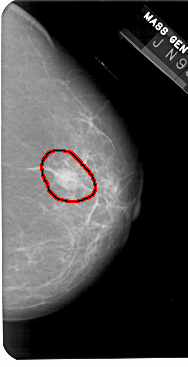

A_1436_1.RIGHT_CC

RIGHT_CC LINES 5491 PIXELS_PER_LINE 2806 BITS_PER_PIXEL 12 RESOLUTION 43.5 OVERLAY

FILE: A_1436_1.RIGHT_CC.OVERLAY

TOTAL_ABNORMALITIES 1

ABNORMALITY 1

LESION_TYPE MASS SHAPE OVAL MARGINS CIRCUMSCRIBED

ASSESSMENT 4

SUBTLETY 5

PATHOLOGY BENIGN

TOTAL_OUTLINES 1

BOUNDARY